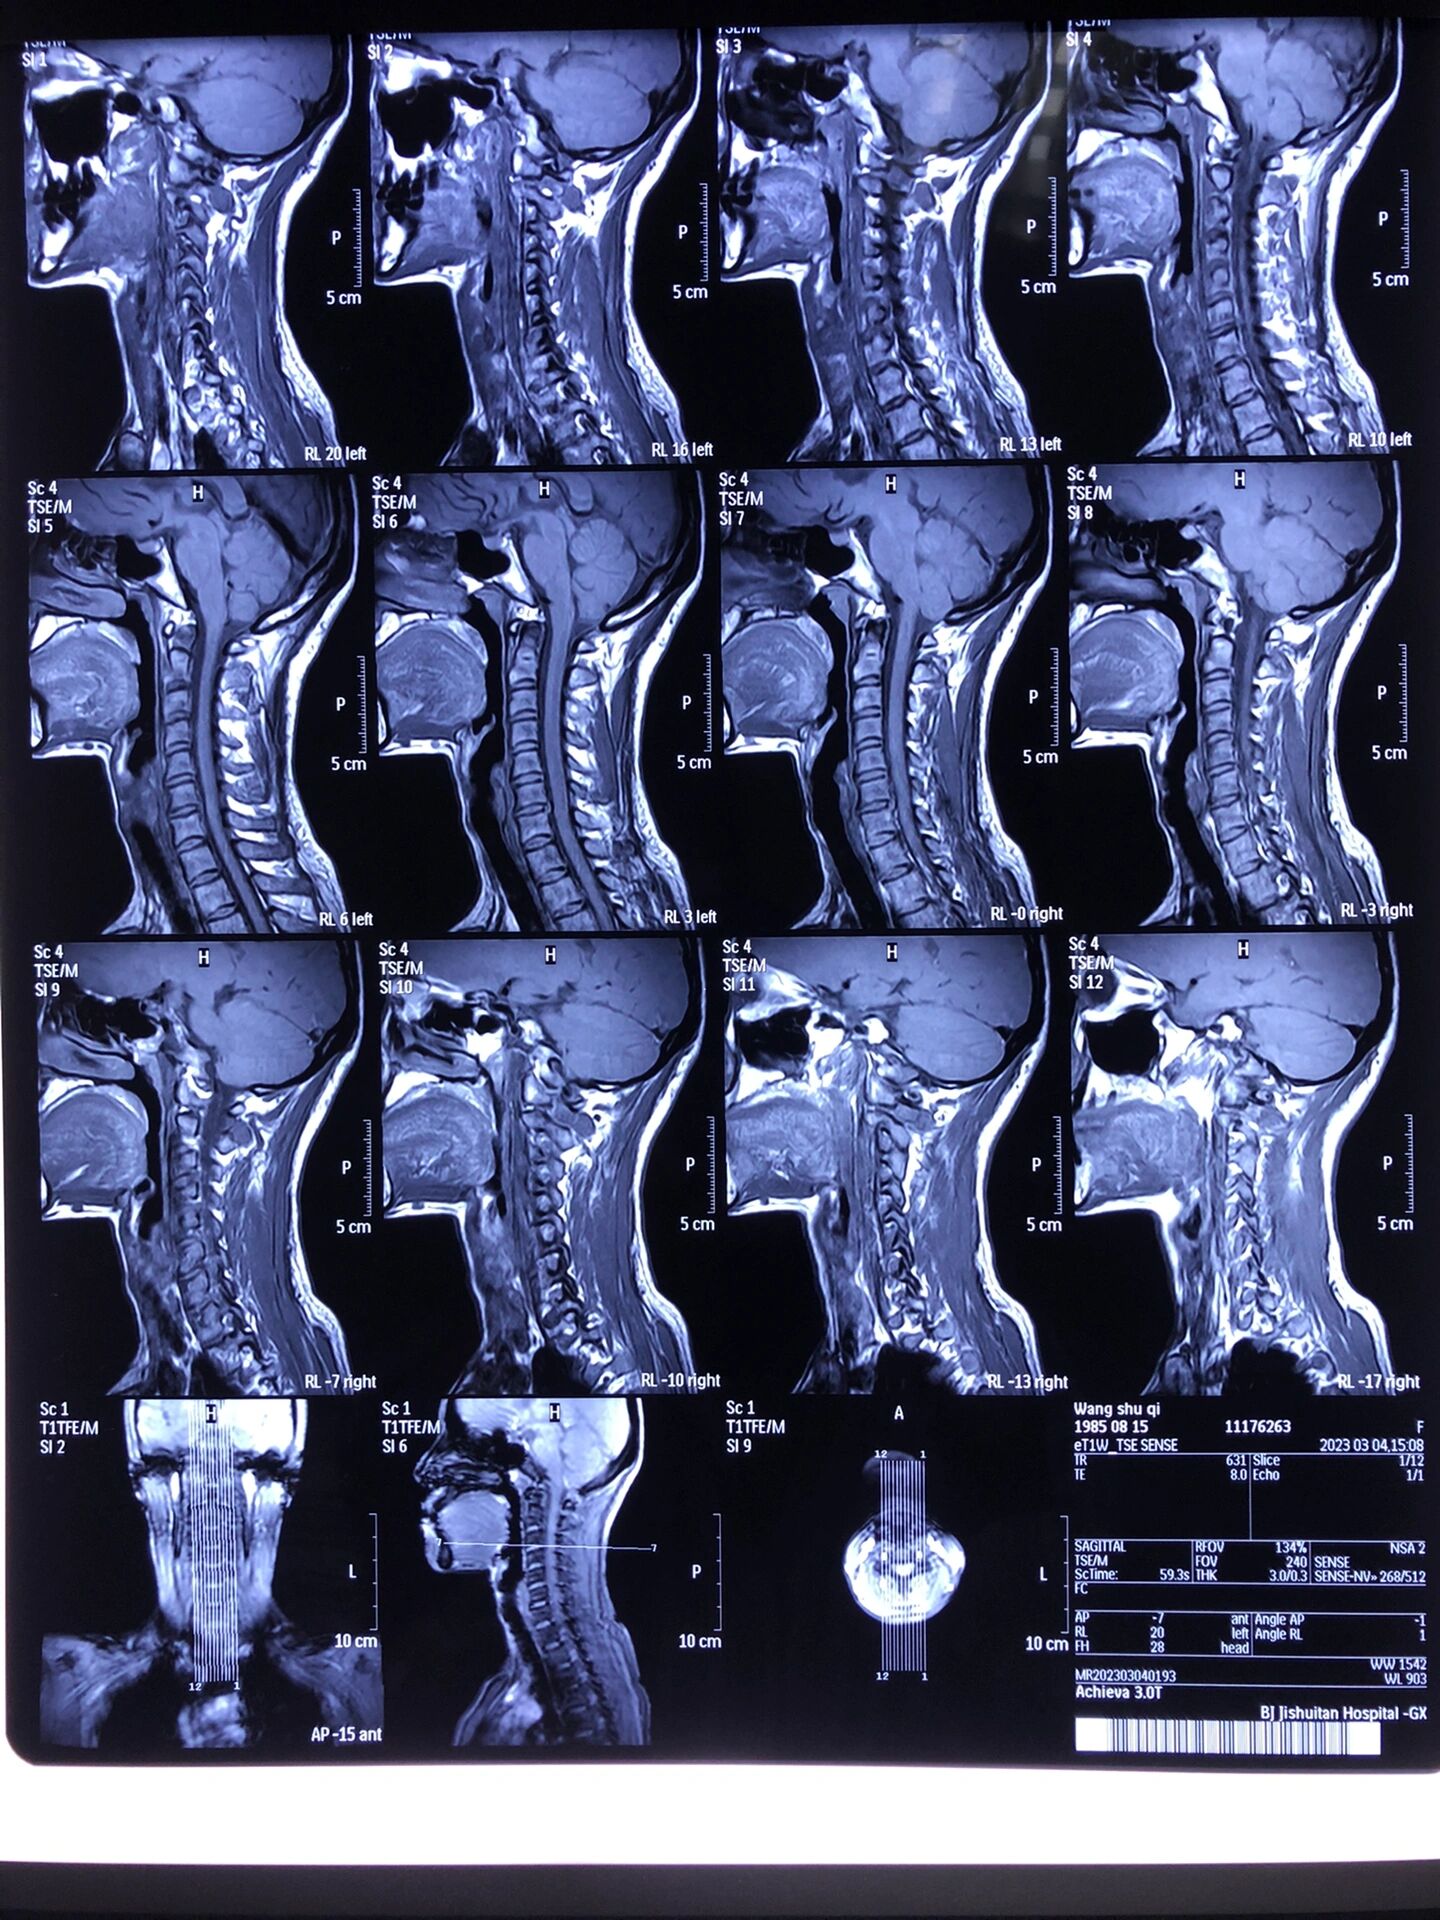

神经根型颈椎病入住积水潭间盘缩小不用手术

图片尺寸1440x1920